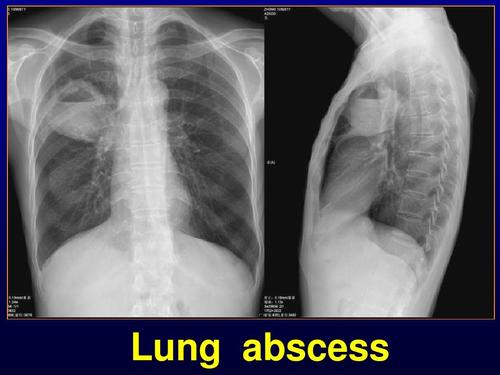

lung abscess

西安交通大学医学院呼吸系统疾病课件 lung abscess.

内科 肺 脓 肿 lung abscess 云南省第一人民医院呼吸科